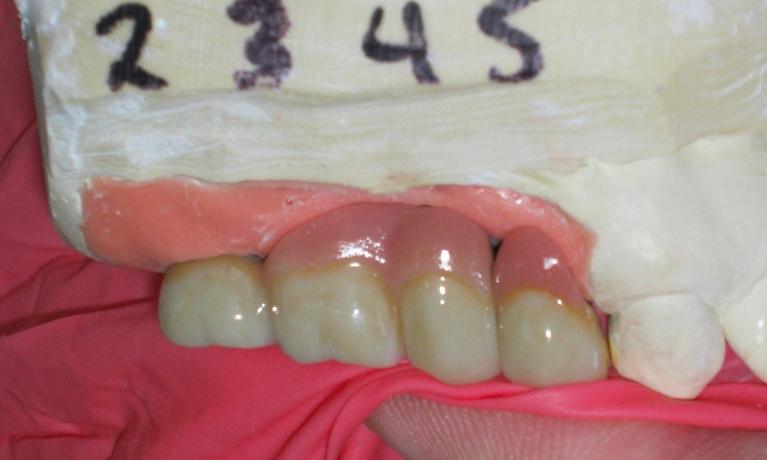

We take great pride in the services we perform in our office. We always try to not only meet your expectations, but we also try to exceed them. There are many types of services that we perform in our office, as well as others that we perform in coordination with highly skilled specialists. We have compiled a few examples of the treatments that we have performed. We are proud to say that these are the usual results our patients expect to see.

The photos are not retouched, nor are they taken by a professional photographer. These are just the routine treatment photos that we take and the results that we see every day. They are by no means a comprehensive catalog of the procedures that we perform. They are just a small sample of some of the results you can expect when you seek treatment in our office.